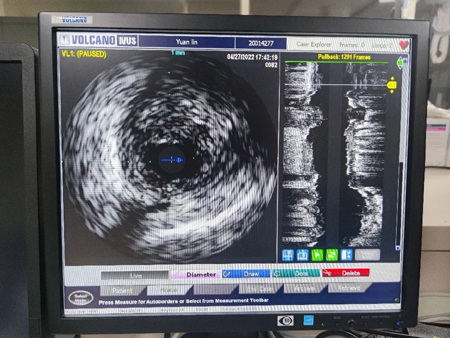

IVUS可以看到桥血管狭窄最严重部位斑块的形态

经过多次充分激光消蚀后,管腔狭窄明显减轻,IVUS也终于可通过狭窄病变到达远端,观察到管腔内斑块负荷重,形态上相对稳定,随后植入支架,最终效果非常满意,无并发症出现。